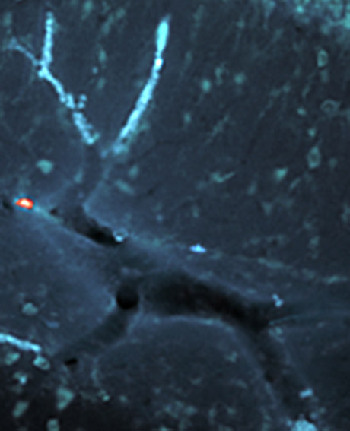

大脑血管图中惊现“红鼻驯鹿”

更有趣的是,科学家在给它做出标记后,图像中出现了一个红色亮点,它恰好构成驯鹿的红鼻头!

研究人员拉卡表示:“有的时候自然界就是这样,我们在工作之余获得了这样一份惊喜。虽然它于科学突破没什么重大意义,但它给我们带来了不少乐趣。”